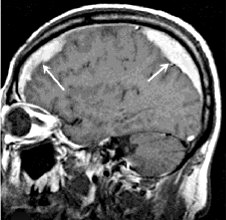

Наиболее часто субдуральные гематомы наблюдаются вокруг верхних и боковых поверхностей лобных и теменных долей головного мозга[3][8]. Также СДГ могут встречаться в задней черепной ямке, по ходу серпа мозга и намёта мозжечка[3]. В отличие от эпидуральных гематом, ограниченных швами черепа, субдуральные гематомы могут широко распространяться в полости черепа вдоль поверхности головного мозга, повторяя её форму и останавливаясь лишь в области отростков твёрдой мозговой оболочки.

При компьютерной томографии субдуральные гематомы имеют классическую серповидную форму, однако, могут выглядеть и линзовидно, особенно в начале кровотечения; это может вызвать затруднения в дифференциальной диагностике субдуральной и эпидуральной гематом. Более достоверным признаком субдуральной гематомы является её относительно большая распространённость по ходу полушария головного мозга с преодолением швов черепа, в отличие от эпидуральной гематомы. Субдуральная гематома также может выглядеть как «наслоение» повышенной плотности по ходу намёта мозжечка; такая гематома может быть хронической и стабильной, и косвенными минимальными признаками кровоизлияния могут служить сглаженность прилегающих борозд и медиальное смещение границы между серым и белым веществом.